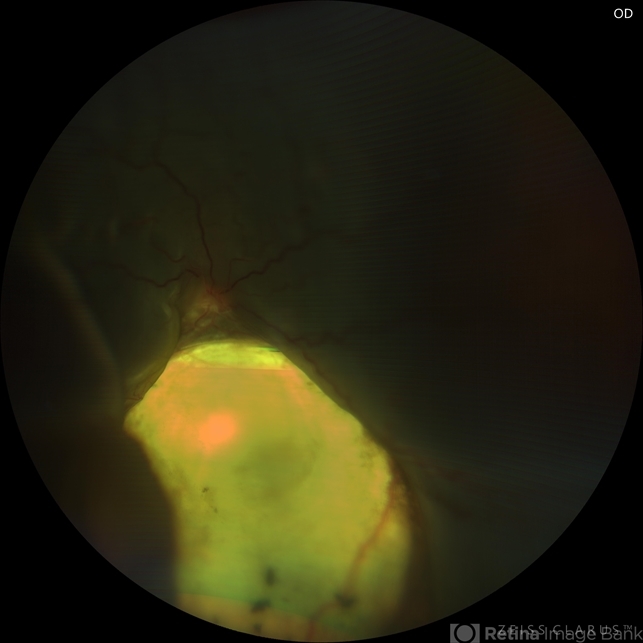

- coloboma of choroid, pre-op

- 17-year-old female with RC coloboma with total bullous retinal detachment